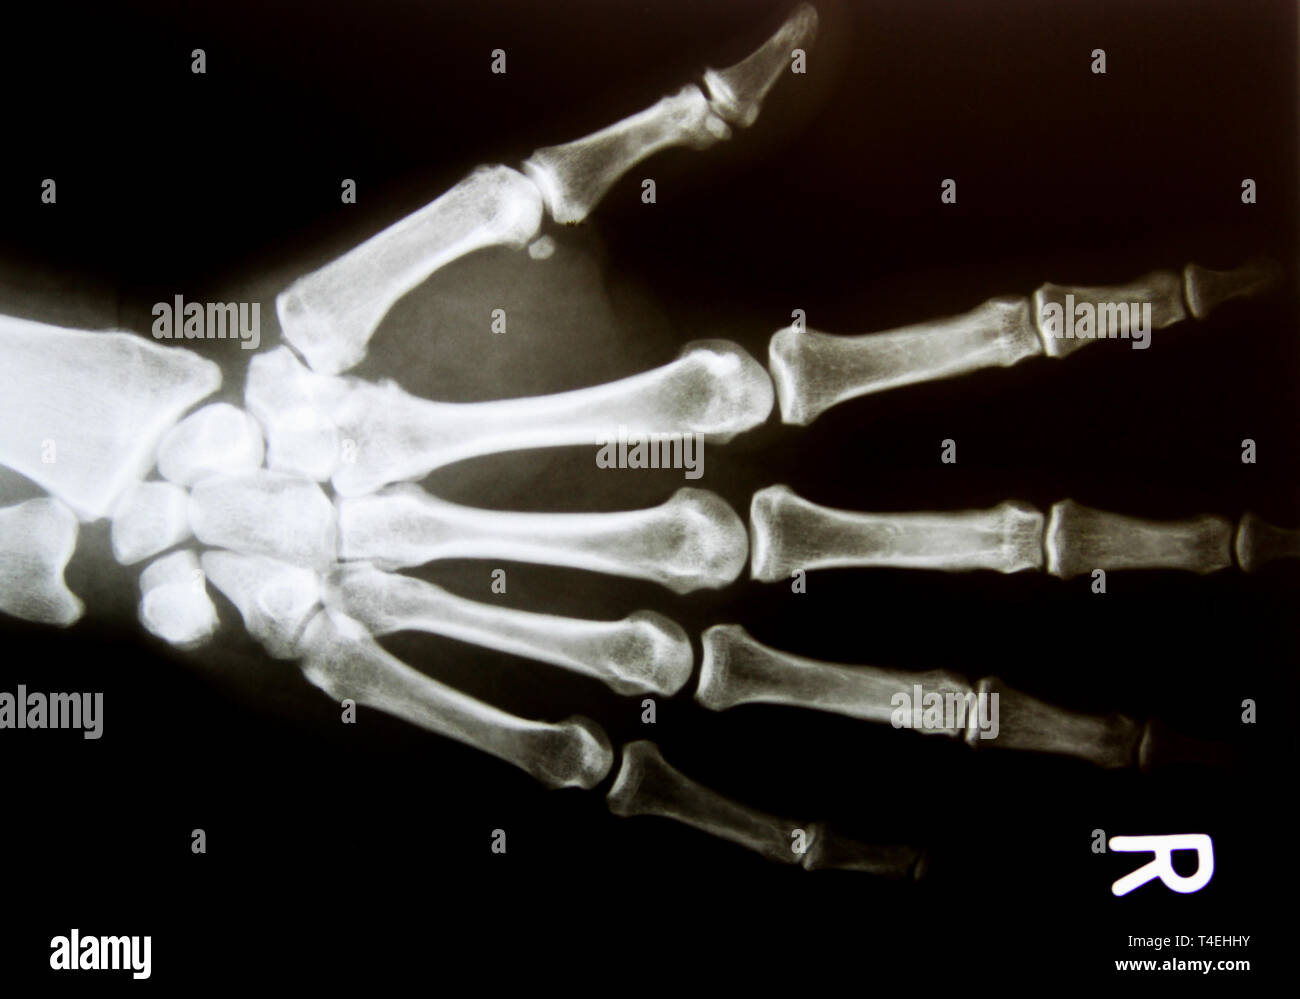

The hand comprises the metacarpal and phalangeal bones. — key points. On “anatomical parts” you can choose between two types of labels: A systematic approach will help those reporting msk. Fractures and dislocations are usually straightforward to identify, so long as the potentially injured bone is fully visible in 2 planes. anatomía normal by miguel ángel calderón santisteban. Case contributed by andrew murphy. Arthropathies of hands & feet by john fitzpatrick. normal hand | radiology case | radiopaedia.org.

Xray of human Hand fingers top view. Xray of male hand and wrist. X Normal Hand X-Rays On “anatomical parts” you can choose between two types of labels: The hand comprises the metacarpal and phalangeal bones. normal hand | radiology case | radiopaedia.org. Fractures and dislocations are usually straightforward to identify, so long as the potentially injured bone is fully visible in 2 planes. Arthropathies of hands & feet by john fitzpatrick. Case contributed by andrew. Normal Hand X-Rays.